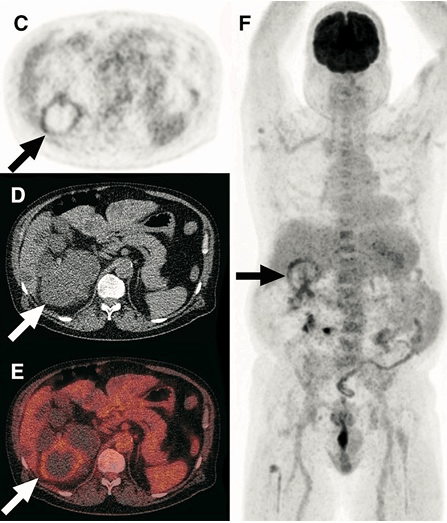

A alta da IRA realmente significa recuperação… ou apenas o começo da DRC futura? Albuminúria, reintrodução de IECA/BRA, iSGLT2 e seguimento precoce podem mudar completamente o prognóstico pós-IRA — e muita gente ainda foca só na creatinina da alta. Esse artigo do Clinical Kidney Journal traz 10 pontos práticos que todo nefrologista deveria revisar no seguimento pós-IRA.